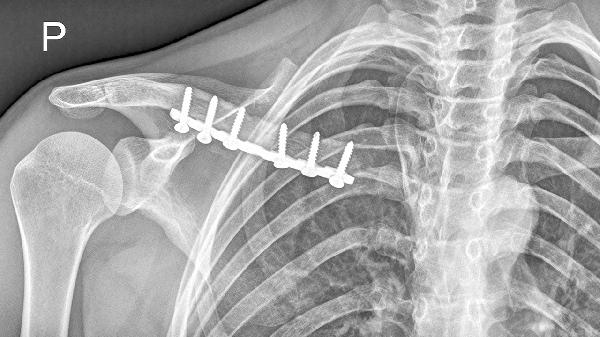

2、外伤因素

锁骨骨折愈合不良是常见原因,尤其多见于儿童青枝骨折或成人粉碎性骨折后。骨折错位愈合会导致局部骨痂增生或短缩畸形,可能伴随肩关节活动时弹响。需通过X线确认愈合状态,严重畸形需手术截骨矫正。